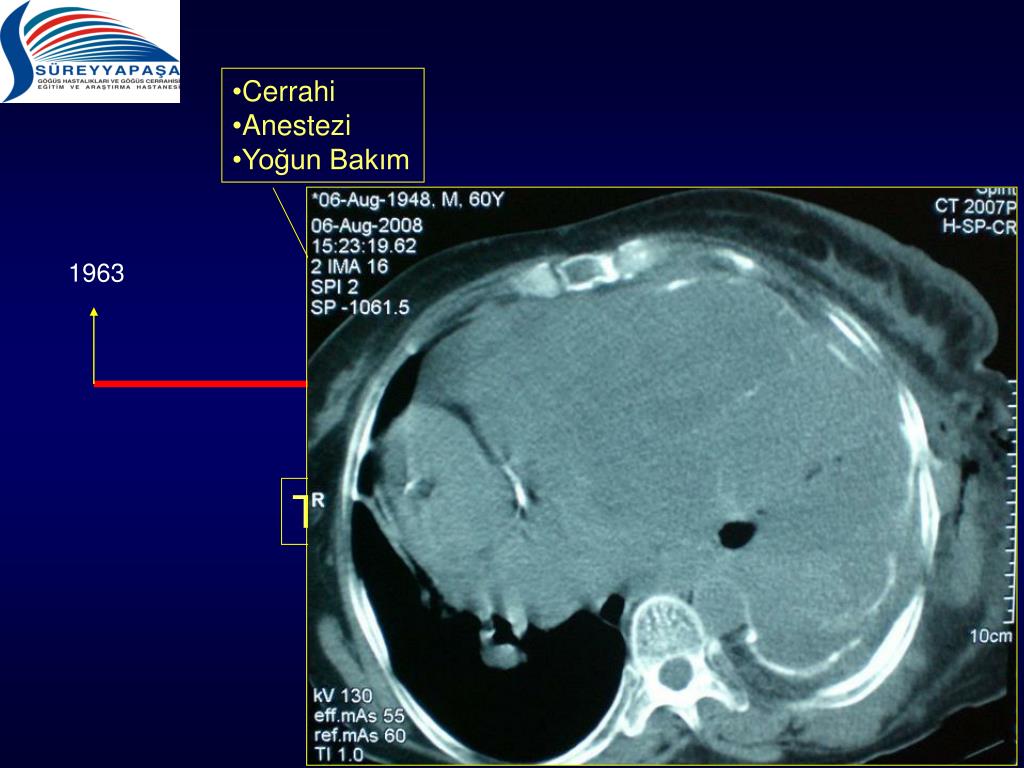

15. Cerrahi • Anestezi • Yoğun Bakım 1963 1983 2007 2009 2006 Teknik Hazırlık

16. Cerrahi • Anestezi • Yoğun Bakım 1963 1983 2007 2009 2006 Teknik Hazırlık

17. Cerrahi • Anestezi • Yoğun Bakım 1963 1983 2007 2009 2006 Teknik Hazırlık

18. Cerrahi • Anestezi • Yoğun Bakım 1963 1983 2007 2009 2006 Teknik Hazırlık

19. Cerrahi • Anestezi • Yoğun Bakım 1963 1983 2007 2009 2006 Teknik Hazırlık

20. Cerrahi • Anestezi • Yoğun Bakım 1963 1983 2007 2009 2006 Teknik Hazırlık